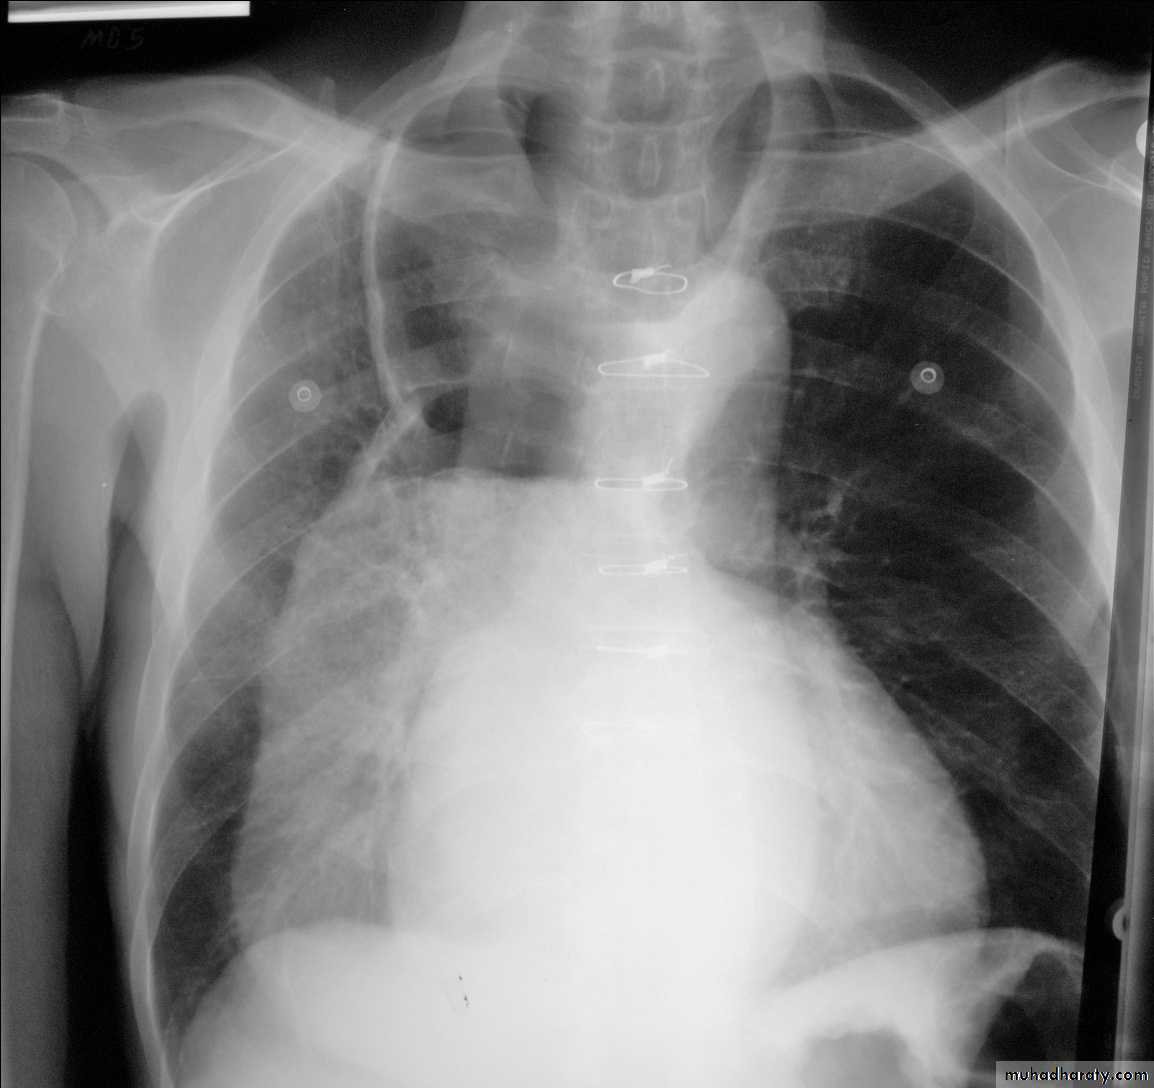

• A chest X-ray may be abnormal in late disease, with widening of the mediastinum from gross oesophageal dilatation and features of aspiration pneumonia.

Chest X-ray in achalasia